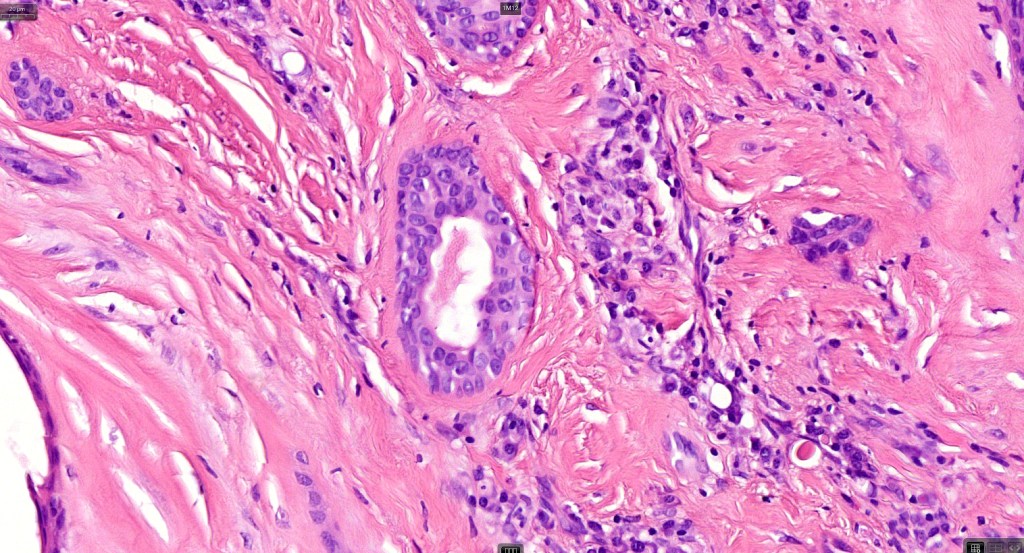

Histological features

•Well circumscribed unencapsulated, nodular/multinodular silhouette composed of an admixture of epithelial & mesenchymal elements

•Mixed epithelial component including nests & cords of epithelium with abundant, eosinophilic cytoplasm & small vesicular nuclei

•Glandular differentiation sometimes showing apocrine differentiation

•Myoepithelial layer in glandular foci

•Ductal differentiation

•Mitoses very rare or absent

•No necrosis